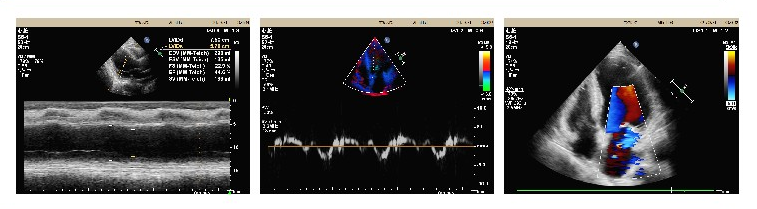

医 术 2021年9月6日 成都东篱医院 心内科李其勇主任带领科室团队 为一位患“扩张型心肌病 ”七十岁爷爷 成功施行“ CRTD植入术” 希望可以治好自己的“心病” 夏爷爷,70岁,十余年前就因活动后心累气促、活动耐受力下降,被当地医院诊断为“心力衰竭”,给予药物治疗后好转。近些年反复发作,后被诊断为“扩张型心肌病 全心增大 EF下降型心衰”,辗转于多家医院,治疗效果微乎其微。1个月前夏爷爷感到病情进一步加重,甚至走几分钟的路都得停一停、缓一缓,身体乏力,精神萎靡,夜间还存在呼吸困难的情况,于8月27日收入我院心内科。 心脏彩色多普勒超声提示:LA55*73*62,LV76,RA59*42,IVS11,EF37%。 腔内电生理图提示:QRS波163.89ms 新技术带来新希望 术前科室医疗组经过反复分析病情与家属沟通后,决定为夏爷爷植入CRTD(心脏再同步化治疗及埋藏式心脏自动除颤器)。 CRT(心脏再同步化治疗起搏器)可以保证心脏的左右心腔重新恢复同步收缩,减少由于心脏扩大导致的瓣膜返流,达到改善心衰,逆转心脏扩大的作用。 ICD(埋藏式心脏自动除颤器)则可以自动识别室性心动过速、室性纤颤等恶性快速心律失常,及时给予电学终止治疗。 CRTD将以上两种功能合二为一,该技术集起搏、治疗恶性心律失常、改善心力衰竭于一体,使慢性心衰病人恢复双心室同步收缩、改善心功能、从而降低心律失常的发作,提高生活质量,降低心衰住院率和死亡率。 CRTD成功植入,老人平安 手术器械的选择,手术的每一个步骤,术中可能出现的危急情况等,科室都做了充分的准备。9月6日,在李其勇主任的指导下,心内科医护团队紧密协作,克服患者靶血管相对细小的困难,最终选择适宜位点,成功植入电极,手术非常顺利。 安置后的CRTD 术后经胸部CT证实患者电级安装到位,程控起搏器各项数据工作良好。切口周围皮肤无红肿、无明显活动性出血疼痛,患者自述症状较前期缓解。从此,夏爷爷的心脏有了一个“新管家”,心功能将逐渐恢复!